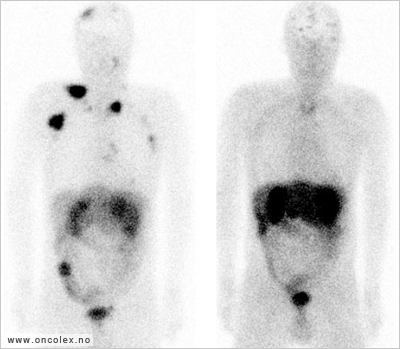

Bildeeksempler behandlingseffekt:

Octreotidscintigrafibilder viser effekt av behandling med 177-Lutetium. Før (venstre) og 1 år etter (høyre). Pasienten sett forfra.